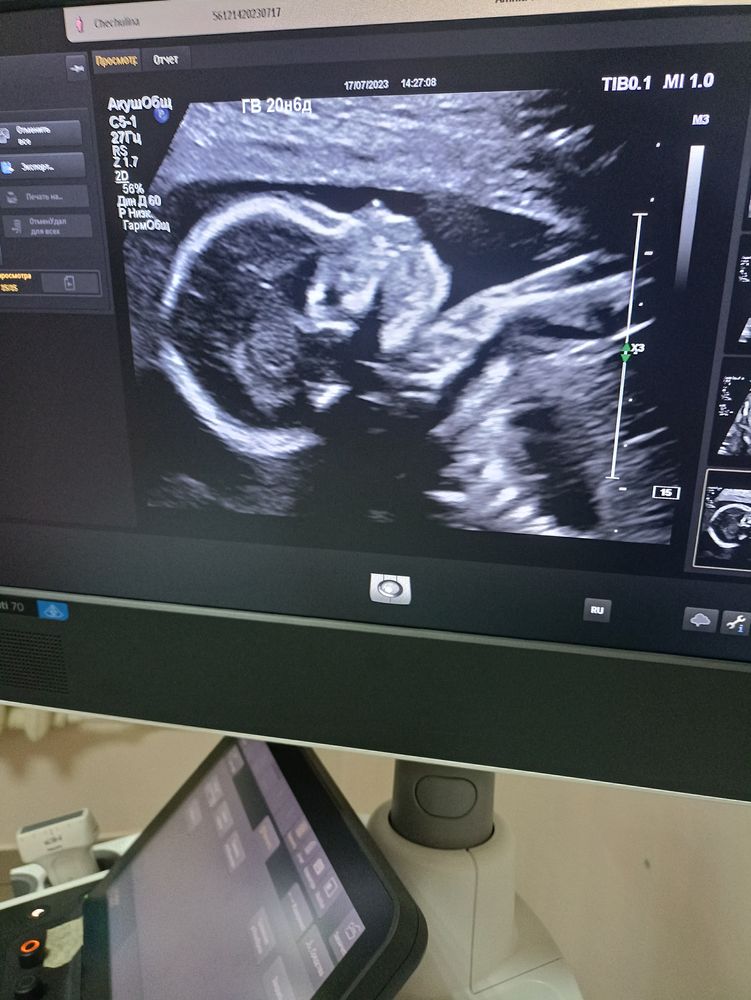

Второй скрининг

Анализы, скрининги

Ура, прошли второй скрининг. Наконец-то моя булочка показала свой пирожочек)) уже 21 неделю всё думаю кто же там в пузе живёт) теперь знаю. На 13 неделе нам предположили малышку, но с высокой вероятностью ошибки.